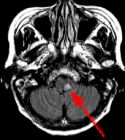

MRI Findings: In the supratentorial regions, some atrophy and chronic small vessel deep white matter ischemic changes were observed (Fig. 1) but no acute lesion or infarct was observed on MR diffusion. In the posterior fossa, however, a subtle small 1 cm hyperintensity can be seen in the left side of medulla on T2 weighted (Fig. 2) and FLAIR images (Fig. 3). This can be seen with an infarct, but its age would remain indeterminate. The MR diffusion image (Fig. 4) shows hyperintensity in the same region consistent with an acute infarct (arrows) as opposed to chronic ischemic changes.

Final Diagnosis: Based on the MR appearance, diagnosis of acute lateral medullary infarct was provided. This is a classic appearance of a posterior inferior cerebellar artery (PICA) infarct (PICA Syndrome), which may have thrombosed.